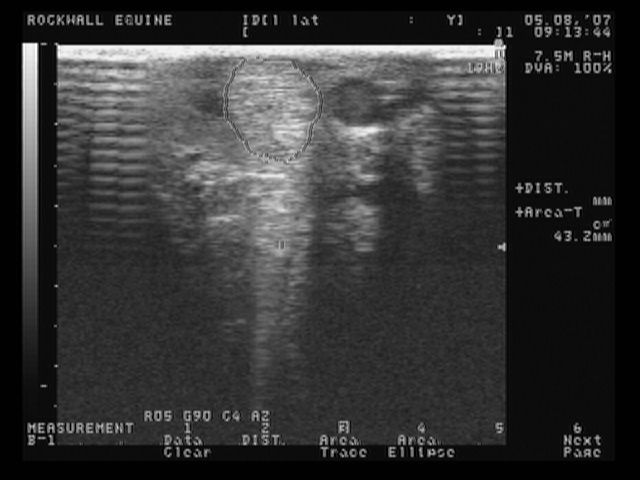

left lateral front normal

These are the most recent ultrasound images of my horses legs, done about 2 weeks ago. The original injury was in January, so he is about 4 months into healing. The left lateral is normal.